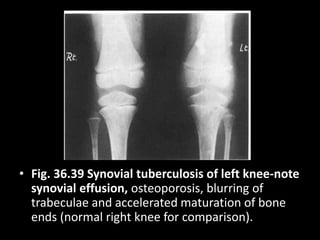

• Fig. 36.39 Synovial tuberculosis of left knee-note

synovial effusion, osteoporosis, blurring of

trabeculae and accelerated maturation of bone

ends (normal right knee for comparison).

• Fig. 36.39Synovial tuberculosis of left knee-note synovial effusion, osteoporosis, blurring of trabeculae and accelerated maturation of bone ends (normal right knee for comparison).